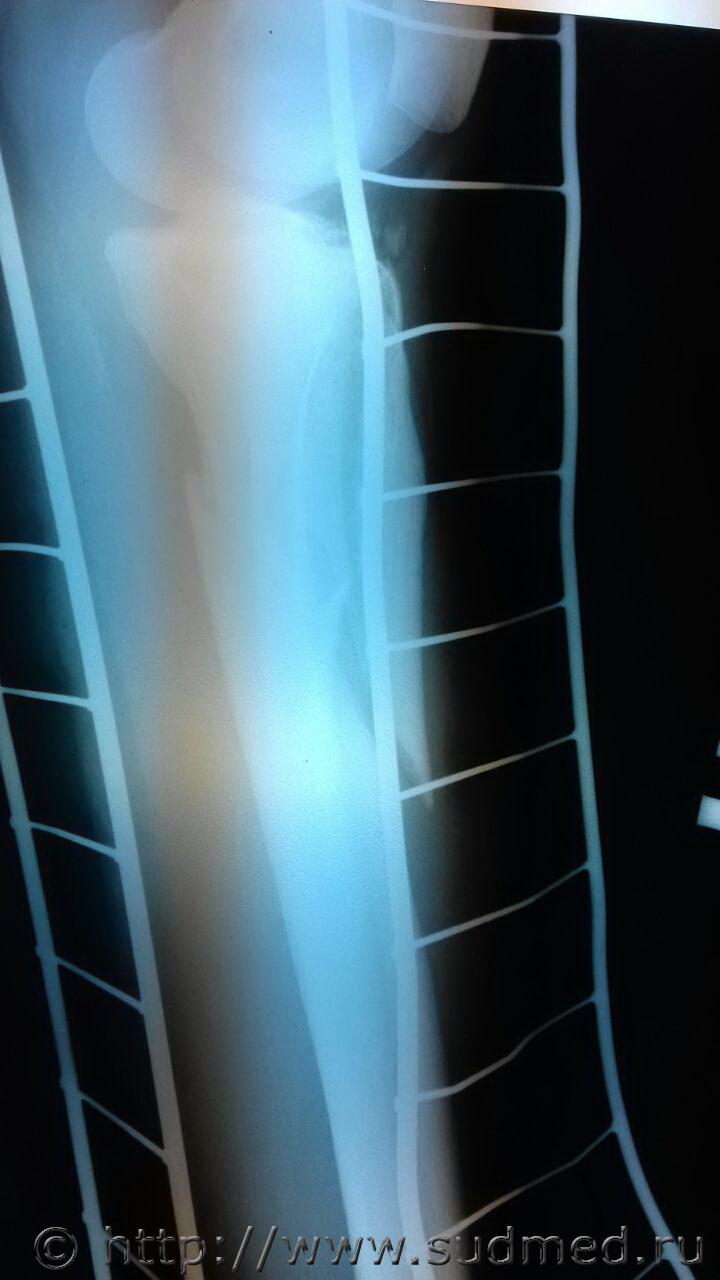

и снова рентгены живых лиц! обстоятельства: ДТП. Пешеход. Нужно определить направление травмирующего воздействия. На коже ничего врачи не зафиксировали

На винтообразый перелом похоже. Поэтому и нет внешних повреждений.

Винт. Кручение проксимального отломка кнаружи, дистального - кнутри.

Винтообразный (спиралевидный) перелом.

Здесь не чистый винт. Здесь винт с изгибом внутрь. Верхний кончик дистального отломка отсутствует (где-то валяется видимо, не видно), продольный перелом проксимального отломка с разрушением суставной поверхности. Да и похоже на подвывих в коленном суставе - суставная щель по высоте разная.

Перелом головки малоберцовой кости виден. Она от чистого кручения по оси большеберцовой кости не ломается.

Благодарю за внимание всех! голень правая. Сомнения потому и возникли, что винт странный через суставную поверхность проходит. А если это сочетание удара и вращения?????

потерпевшая говорит, что шла чз дорогу слева направо, сбита автомобилем. Среди других повреждений: перелом правого скулоорбитального комплекса, основания, ушиб иозга, субдуралка справа. Водитель говорит, что потерпевшая шла по правой части дороги ему навстречу. На авто разбито лобовое стекло, вмятина на капоте справа